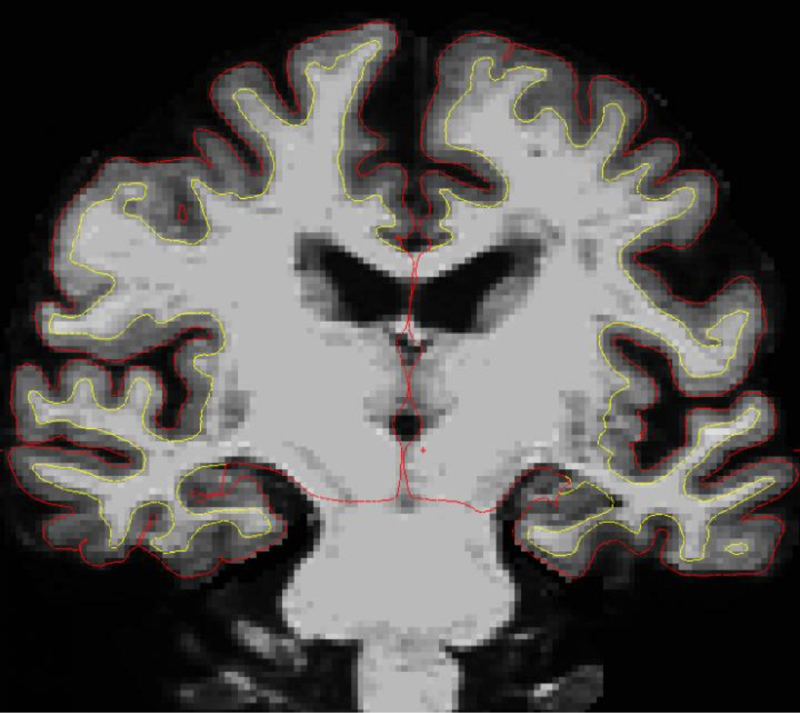

Scientists are learning that SuperAgers’ cortices in the brain (the region between the yellow and red lines) shrink twice as slowly as most peoples' cortices, which may explain why they retain better mental cognition and memory.